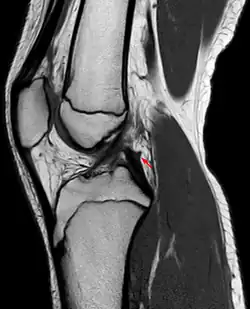

Posterior meniscofemoral ligament on MRI, coronal -

Posterior meniscofemoral ligament on MRI, sagittal -

Posterior meniscofemoral ligament (Wrisberg) behind the posterior horn of the lateral meniscus close to its insertion. Sometimes wrongly interpreted as a meniscal tear.